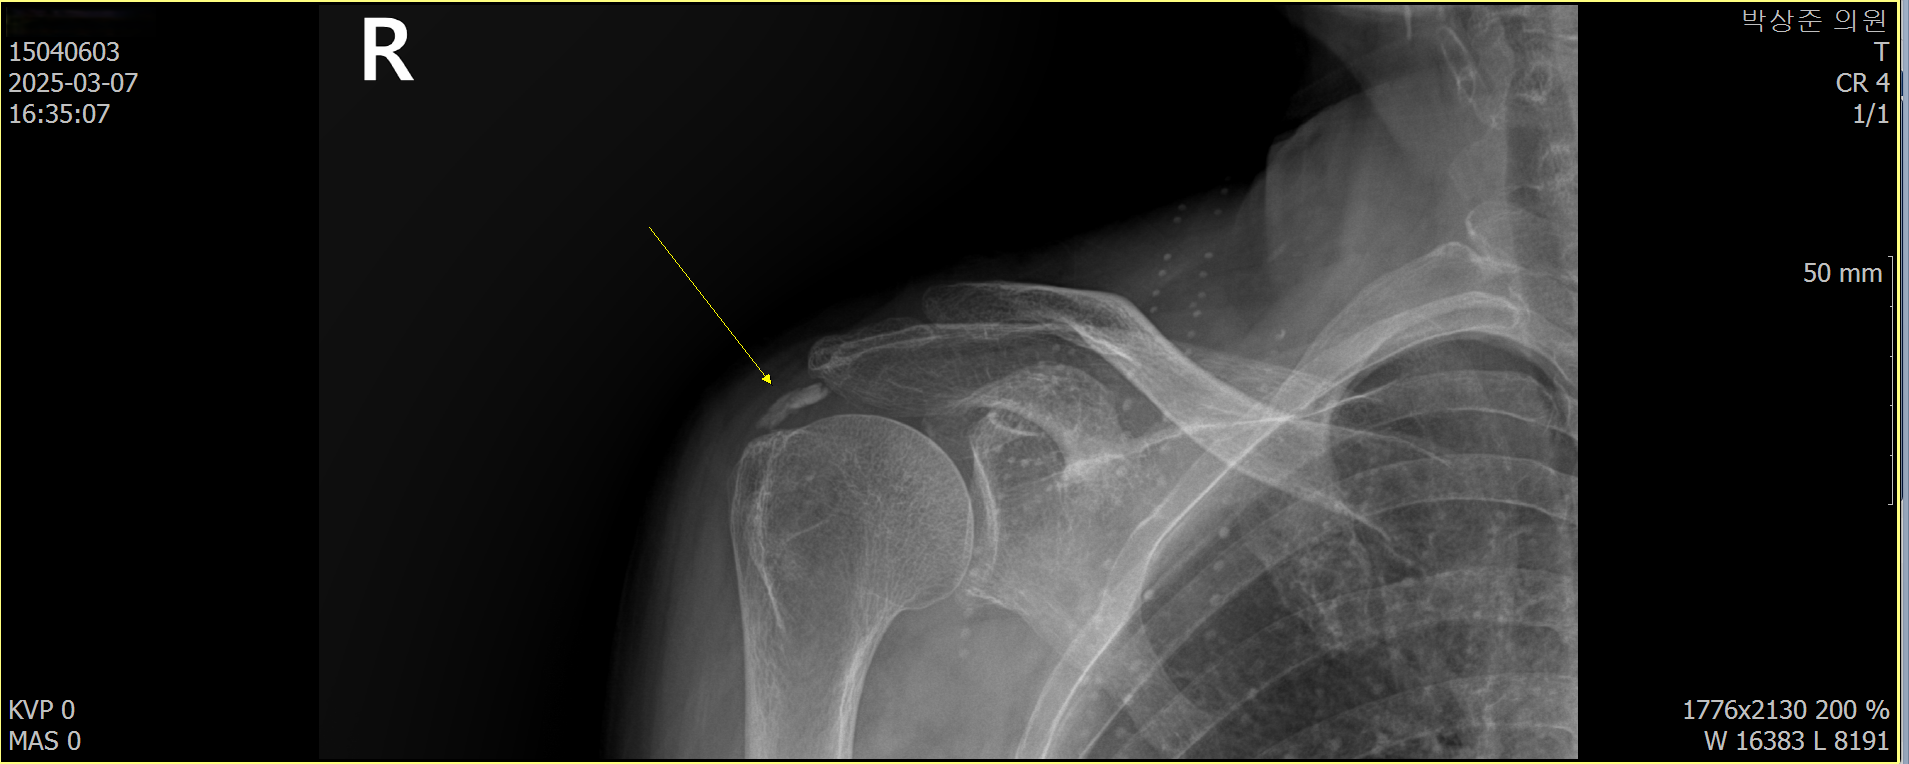

우측 어깨에 커다란 석회가 있습니다.

석회성 건염의 경우 사이즈가 조금만 커도 x-ray에서 쉽게 진단이 가능합니다. 이 환자분의 경우 우측 어깨에 사이즈가 꽤 커다란 석회가 관찰되고 있었습니다.

Before & After (5회 섭회 흡입술 + 체외충격파)

위에 비포 & 애프터 사진에서 보다시피 처음보이던 커다란 석회가 5회의 치료동안 약 90% 가량 사라진것을 확인할 수 있습니다.